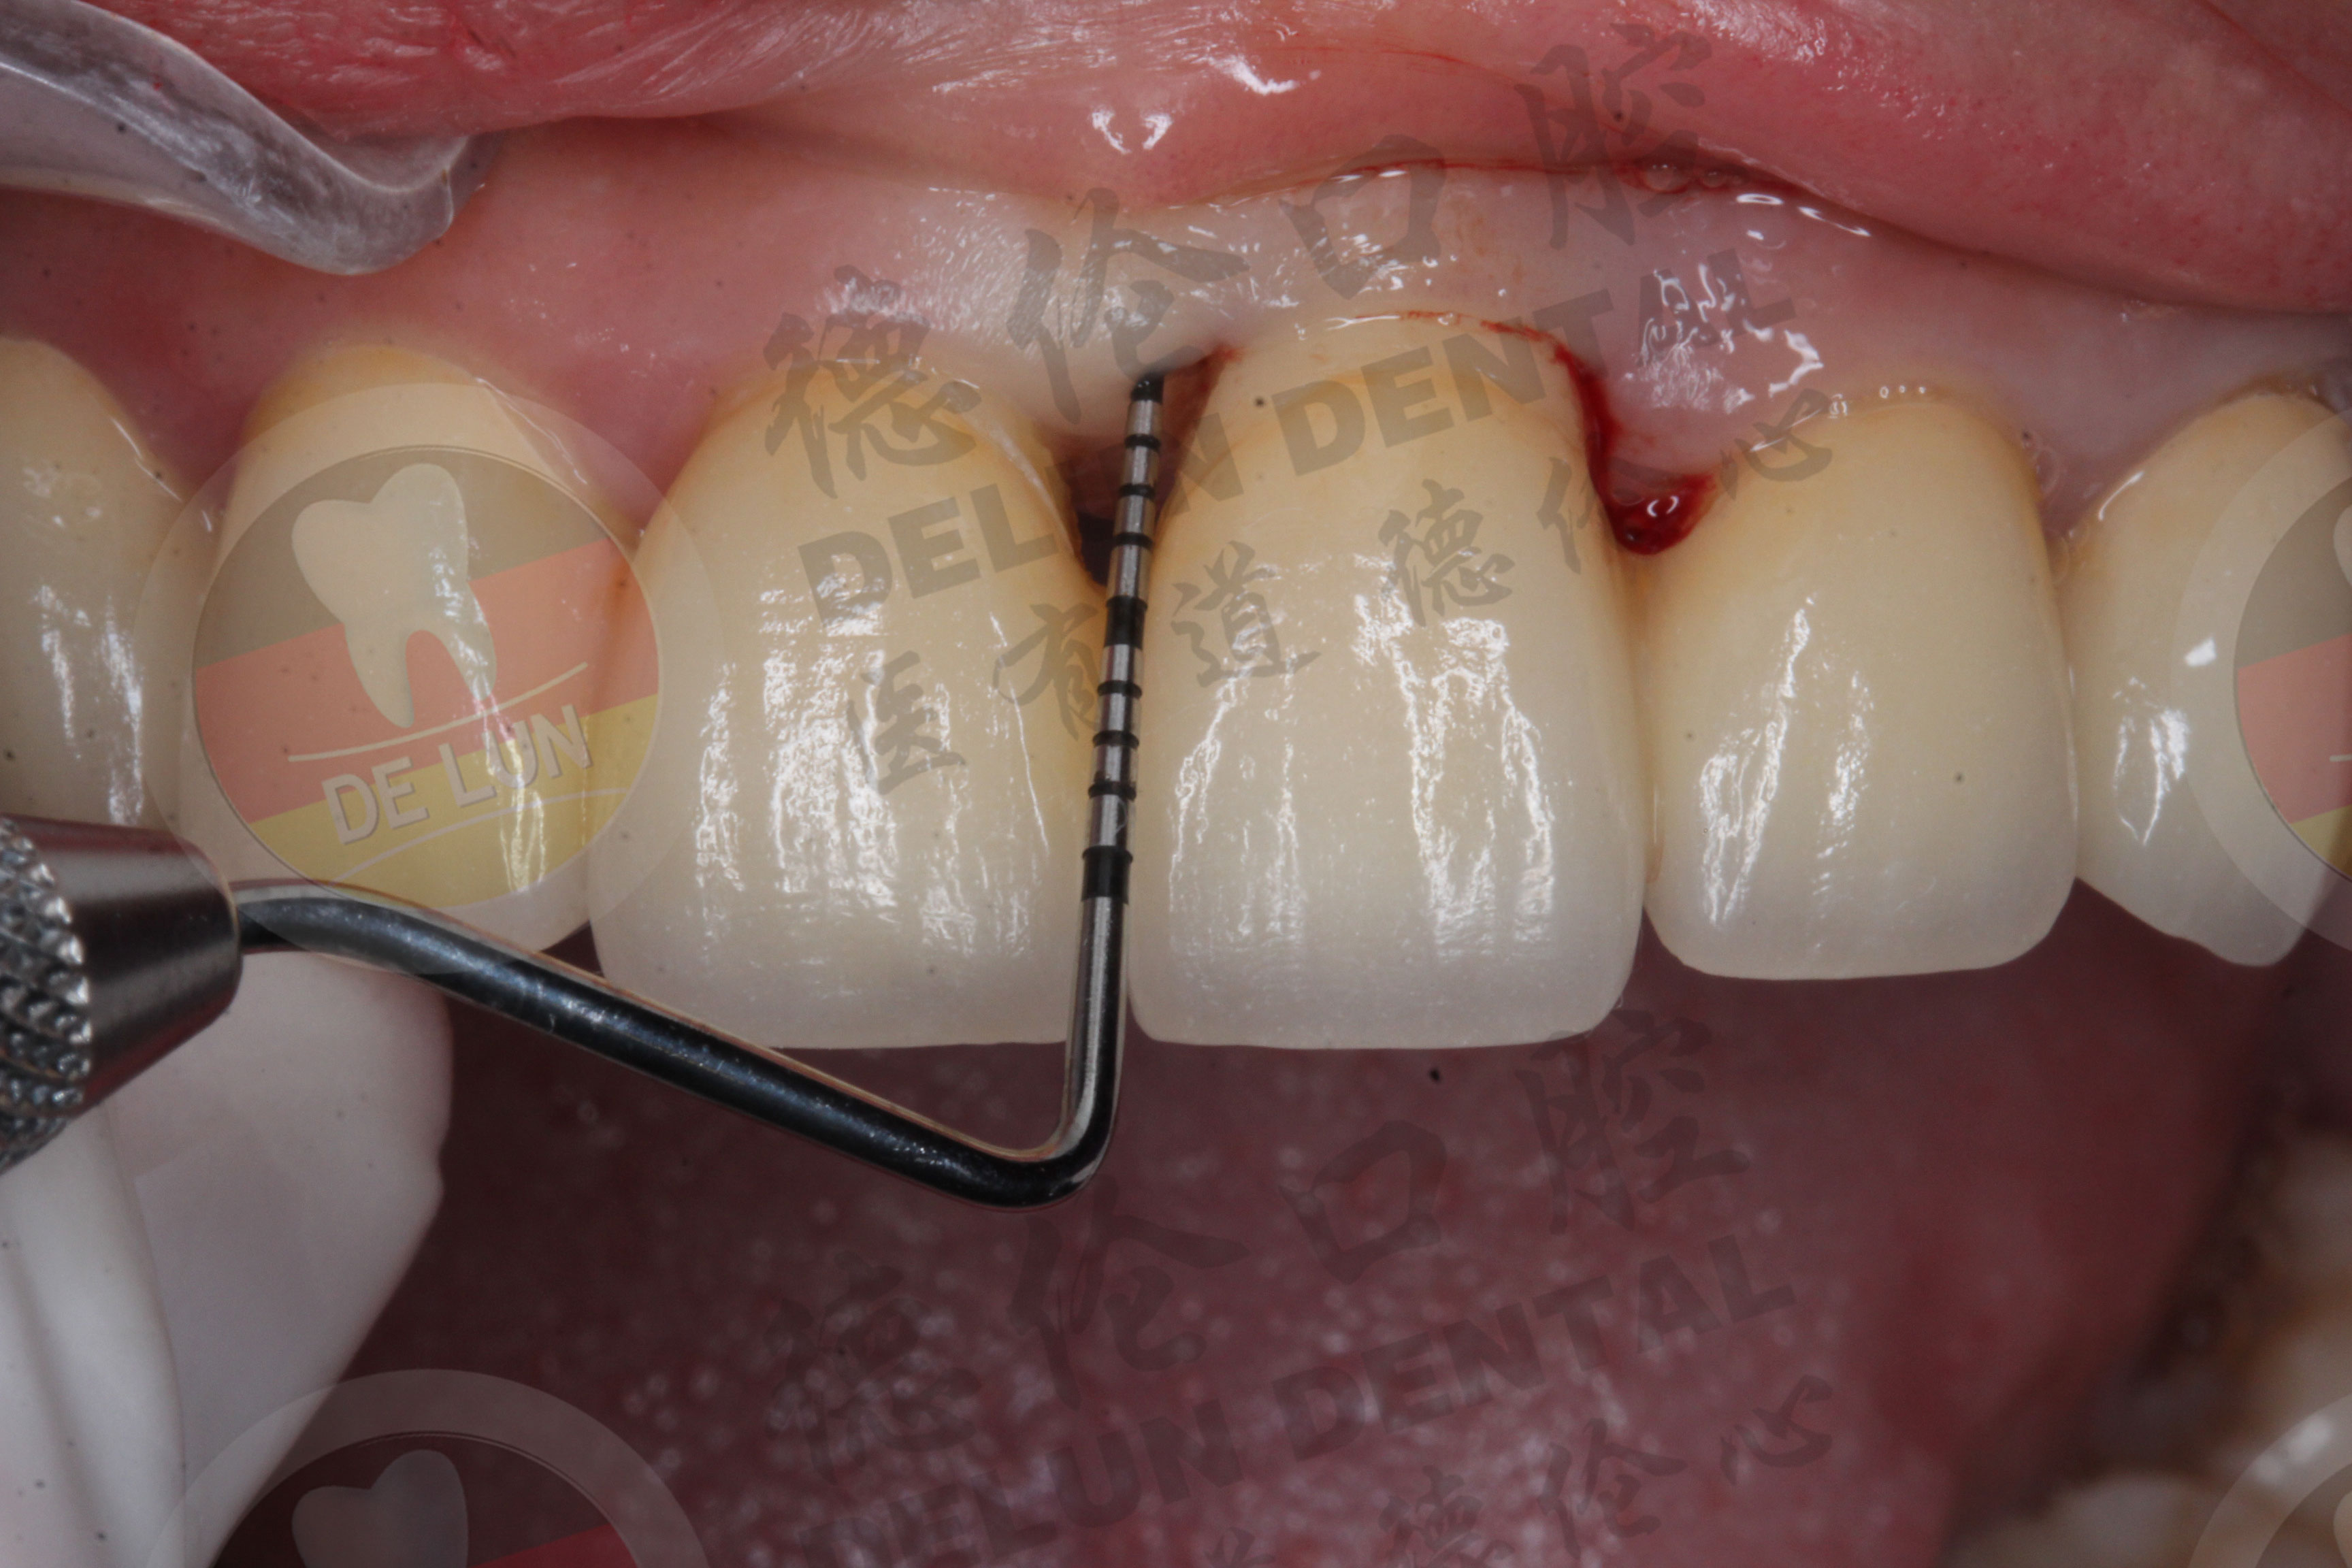

如果牙周炎已经蔓延到牙龈下方的话,单纯用超声波洁牙治疗是不行的,还需要再增加龈下刮治赶走牙周炎,德伦口腔选用——德国牙周治疗仪进行龈下刮治,能更有效破坏龈下生物膜,减少牙周致病因阻止细菌继续对牙周阻止的破坏,促进修复。查看更多德伦口腔牙周炎治疗案例>>>